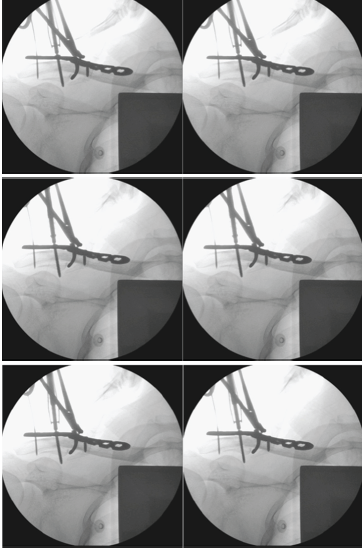

Further dissection was employed to retrieve the inferior fragment with the coracoid ligament attached. The reduction lag screw technique was employed to aid in the reduction of the inferior fragment. A 3.5 mm drill was used for the gliding hole created at the cortical screw hole of the plate – overlying the inferior fragment. A pilot hole was drilled through the inferior fragment using a 2.5 mm drill. An initial 3.5 mm cortical screw was applied to engage the inferior fragment (pilot hole). As the lag-screw was advanced, the inferior fragment was reduced toward the main clavicle fragments (Fig. 3). The reduction of the inferior fragment was then reinforced by tying cerclage braided sutures around the main clavicle fragment.

Figure 3: Reduction of the inferior fracture fragment using the lag screw technique.